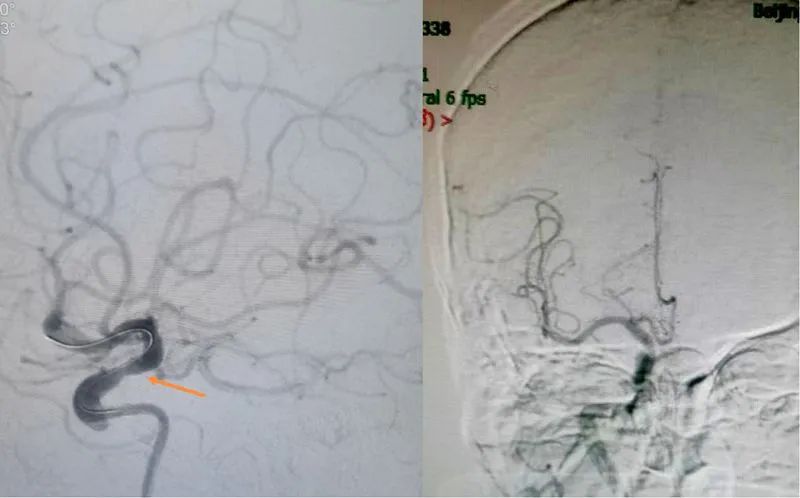

介入手术由孙奉辉主任和孙际典副主任医师实施,造影发现右侧颈内动脉CI段局限狭窄,C6段巨大栓子堵塞,远端血管显影浅淡,由于是主要供血动脉,一旦继发血栓形成、发生大面积脑梗死,预后很差。尽管发病已40小时,超过指南推荐的最长时间窗24小时,但患者病情还在加重,且影像学没有提示大面积梗塞灶,考虑开通手术仍具有可行性。孙奉辉主任在与患者家属进行了术前沟通后,决定实施颅内动脉开通术术。随即,一场挽救生命的战争正悄无声息的展开。

右侧颈内动脉CI段局限狭窄,斑块脱落致C6段堵塞

术中发现栓子非常坚韧,微导丝通过病变部位后,微导管不能通过,传统的支架取栓术及抽吸术均行不通;改用球囊扩张术、多次球囊扩张后立即回弹,此种方法仍行不通。决定应用球囊扩张支架“锚定”住该栓子,经过努力,成功置入支架并将该栓子死死“锚定”在血管壁上,同时未见血管明显残余狭窄,堵塞的血管终于被打开,脑血管造影下见到血流清晰通过。至此,生命的通道被重新开通,整个手术过程患者生命体征平稳。术后该患者症状迅速改善;共住院6天患者出院,出院时NIHSS评分0分,未留明显后遗症。

C6段置入球囊扩张支架,血管完全开通,远端各分支显影良好